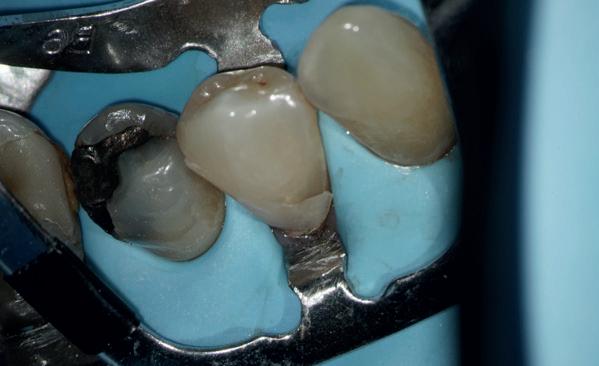

Stap 3: Kies de matrix

Kies de juiste hoogte matrixband van het V3 systeem. Ideaal gezien steunt de matrixband op het tandvlees en eindigt de bovenzijde van de matrix ter hoogte van de randlijst van het element (afbeelding 5).

Stap 4: Plaats de gemodificeerde wig

Plaats een afgeknipte wig. In bijna alle gevallen gebruik ik de Wizard Wedge Wide base. Hierbij is het belangrijk dat de wig geplaatst wordt aan de zijde waar het minste tandweefsel verloren is gegaan. Zorg ervoor dat de wig direct vastloopt. Indien dit niet het geval is, dan dient de wig ingekort te worden met behulp van een schaartje en opnieuw geplaatst te worden. De wig sluit dus de bodem van de box niet af, zoals je normaal gesproken met een wig wel doet (afbeelding 6 en 7).